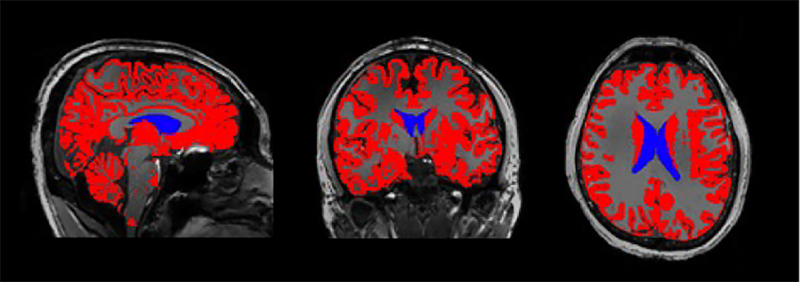

MRI image of the brain with the lateral ventricles colored in blue. The ventricles are filled with cerebrospinal fluid.

Sleep stages were also associated with activity in different brain networks. Compared to light sleep, learning and memory-related brain regions such as the hippocampus and frontal cortex were preferentially active during slow-wave sleep. Considering both results, when the memory network is active during deep sleep, the slow brain waves have a specific effect on the cerebrospinal fluid signal that does not occur during other sleep stages when different brain regions are more active.